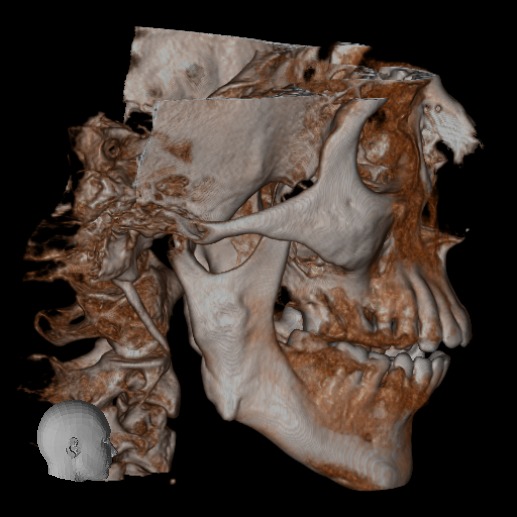

El Centro Radiológico Diagnóstico Oral 3D, es una empresa antioqueña que ofrece a sus pacientes desde el año 2009, tecnología de vanguardia en radiografías tridimensionales con calidad fotográfica. Las posibilidades para mejorar la eficacia en los diagnósticos bucales son evidentes, también lo son las posibilidades de manipulación de imagen. El sistema de imágenes en 3D ofrece detalles sin precedentes, convirtiéndola en la opción idónea para la mayoría de aplicaciones odontológicas, incluyendo implantes, tratamiento de conductos, ortodoncia, odontopediatría, periodoncia y cirugía

El mayor beneficiado con el uso de esta tecnología es el paciente, el cual podrá ser evaluado en todas sus dimensiones con una baja dosis de radiación, con un costo accesible y sin contaminar  el medio ambiente. Dependiendo de la necesidad del paciente, hay varios tipos de tomografías y los especialistas en el área odontológica hacen uso de ellas según su especialidad.

Evaluación de patologías dentales y maxilofaciales

Diagnóstico de traumatismos dentales y maxilofaciales

Evaluación pre y postoperatoria de cirugías maxilofaciales